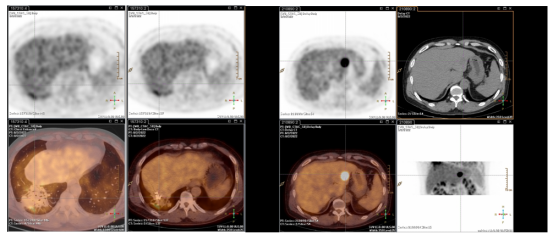

2022.08PET-CT见肝左外叶糖代谢增高,SUV值为10.8。粒子植入术后膈肌上方局限性放射性肺损伤,自行好转。

image.png

图8 影像评估提示肝左外叶糖代谢增高